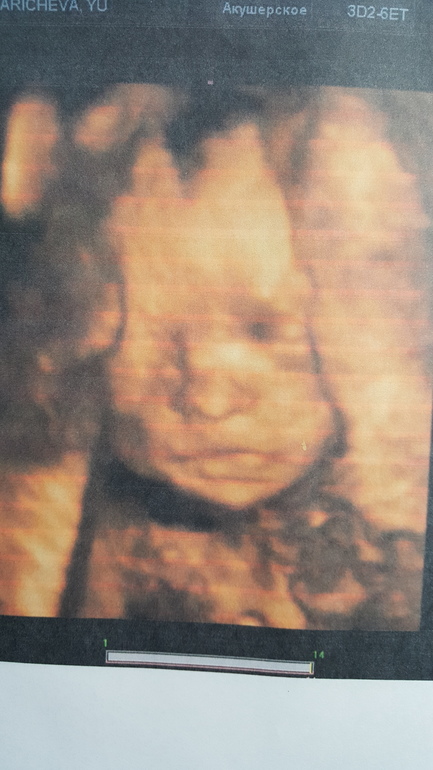

Вот и сходили мы на 2 плановый скрининг на 22 недели,а по месячным 26.Наша дочурка так не отрастила писюн,чему мы уже рады))малышуля уже весит 452 гр и лежит головкой вниз.Все узи она была сама активность,не секунды покоя все поварачивалась спиной,махала и сосала пальчик,Узитка сказала что она акробатка у нас.Чуть растроила новость что у шеи обвитие,но свободное,я надеюсь что малышка распутается еще.Ну,а так мы с папой очень рады нашей девочке и дурацкая улыбка у нас не сходит целый день, и милые фото на память.